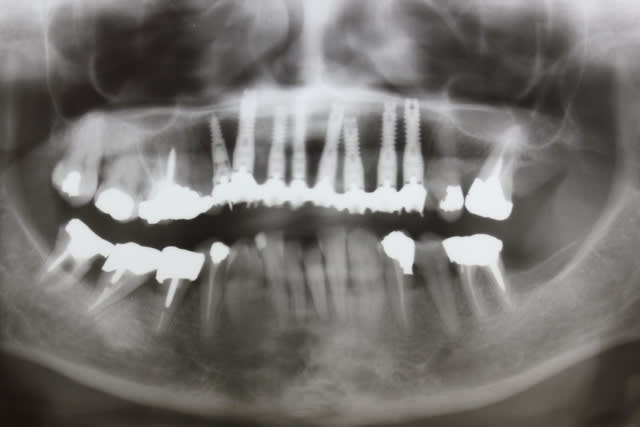

Un peu de travail réalisé - j ai assisté et c est lui qui posait bien sûr - avec un Confrère pour vous dire que je ne suis pas seul à pouvoir poser des disks

Implanto en 2 tps

tps 1 pose du ptérygo et de l implant en 15 et extraction de la 16 avec PRFs + nanobone . Intégration 6 mois pour que le max de nano ossifie

tps 2 extraction 13 11 et pose d implants en 13 12 11 et 16... 16 un monodisk 11G2DM9 et mise en charge immédiate sur 16 11 12 13 et différée sur 18 15

D où plus grande sécurité puisque 4 implants non intégrés sont reliés par la prothèse immédiate avec 2 implants déjà intégrés

CQFD